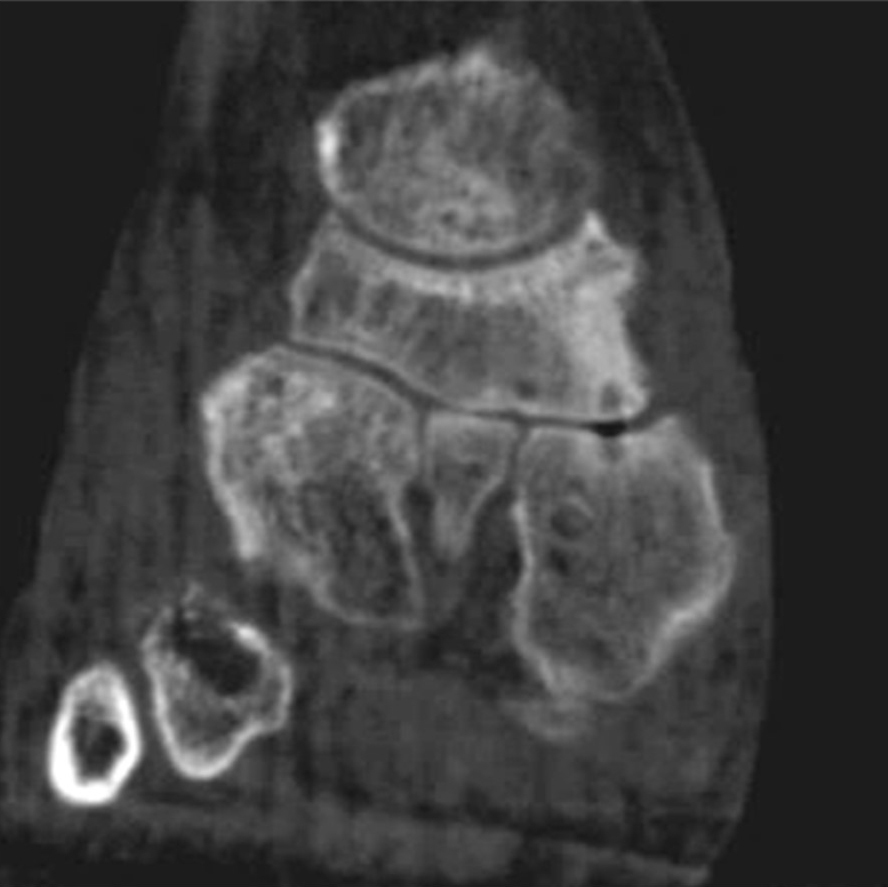

Abbildung 2.3.

Klärung bei Schmerzen im rechten OSG bei OCL an der medialen Talusschulter. Z. n. OSG-Distorsion vor 2 Jahren und Z. n. OSG-Fraktur / Syndesomosenruptur. Ausgedehnte OCL, hier jedoch kein erhöhter Knochenmetabolismus; lediglich Nachweis einer Stressreaktion im Bereich der Synchondrose eines Os trigonum als Schmerzursache.

Zum Lesen der Bildbeschreibung und zur Vollansicht bitte das Bild anklicken. Bild: H. C. Rischke